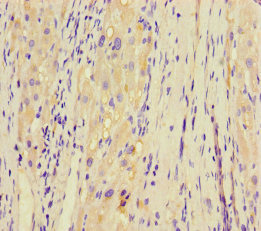

ApplicationELISA, IHC; Recommended dilution: IHC:1:20-1:200